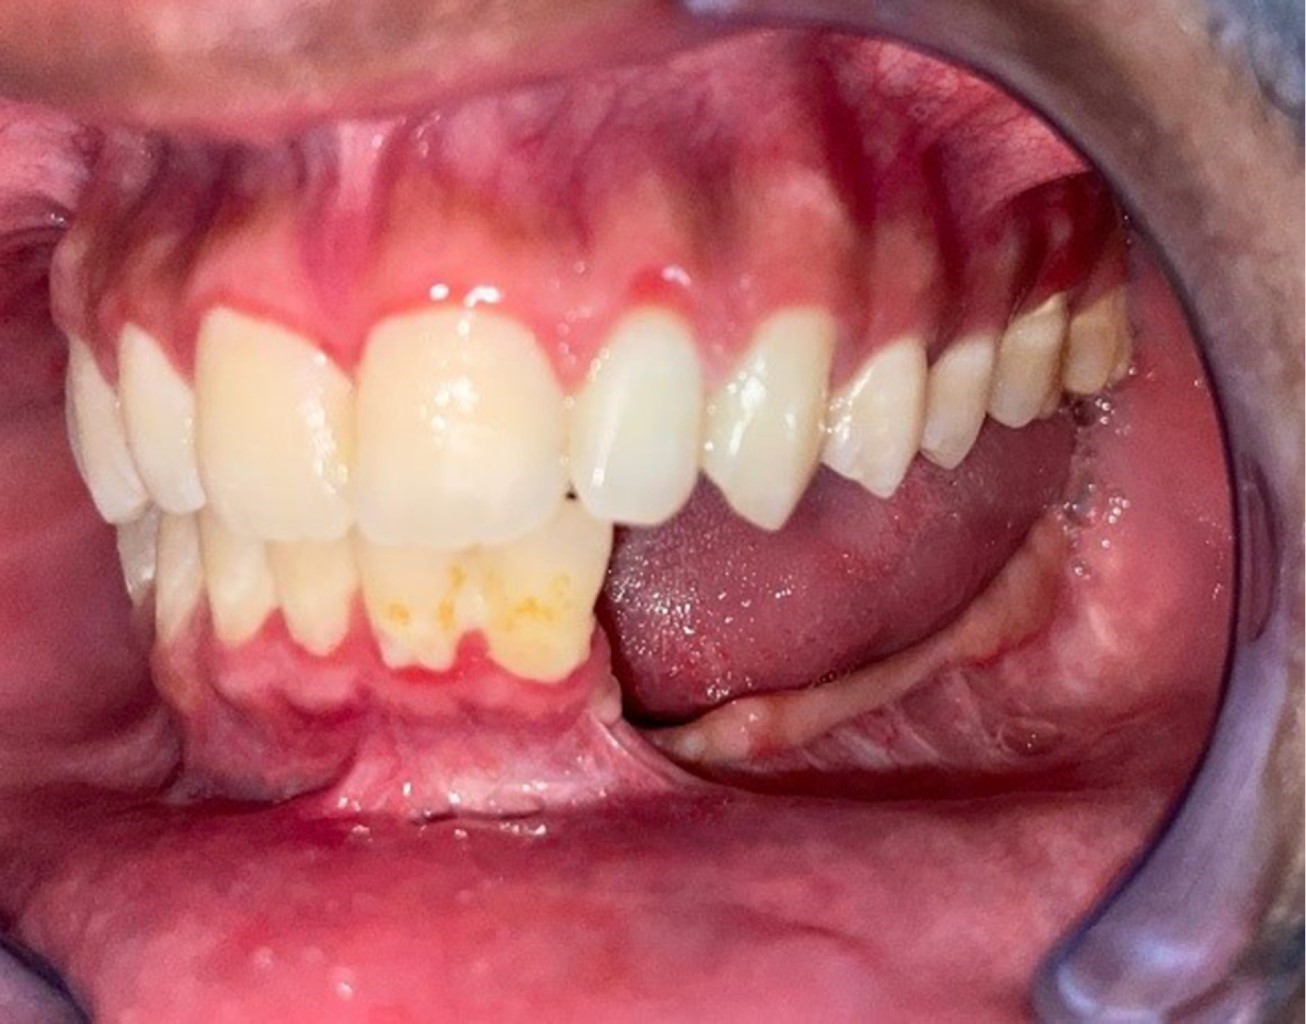

Se comprobó la adaptación mediante movimientos de apertura y cierre, posterior al cierre de tejido blando por planos, fue llevado a la unidad de cuidados intermedios con sonda nasogástrica, la cual fue retirada a los 21 días con una dieta nutricional y evaluación cada 48 horas evidenciando una adecuada cicatrización y apertura bucal progresiva, ligera laterodesviación hacia la derecha que fue corregida con tornillos IMF y ligas intermaxilares, se logró conseguir una adecuada simetría y función con 35 mm de apertura bucal (Figuras 6, 7 y 8).

Figura 8